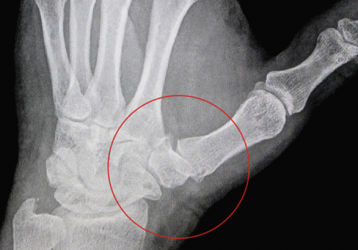

Артроз большого пальца руки: лечение медикаментами и физиотерапия

Как лечить большой палец на руке в случае артроза. Медикаменты и мази для облегчениям состояния. Перспективы полного выздоровления.